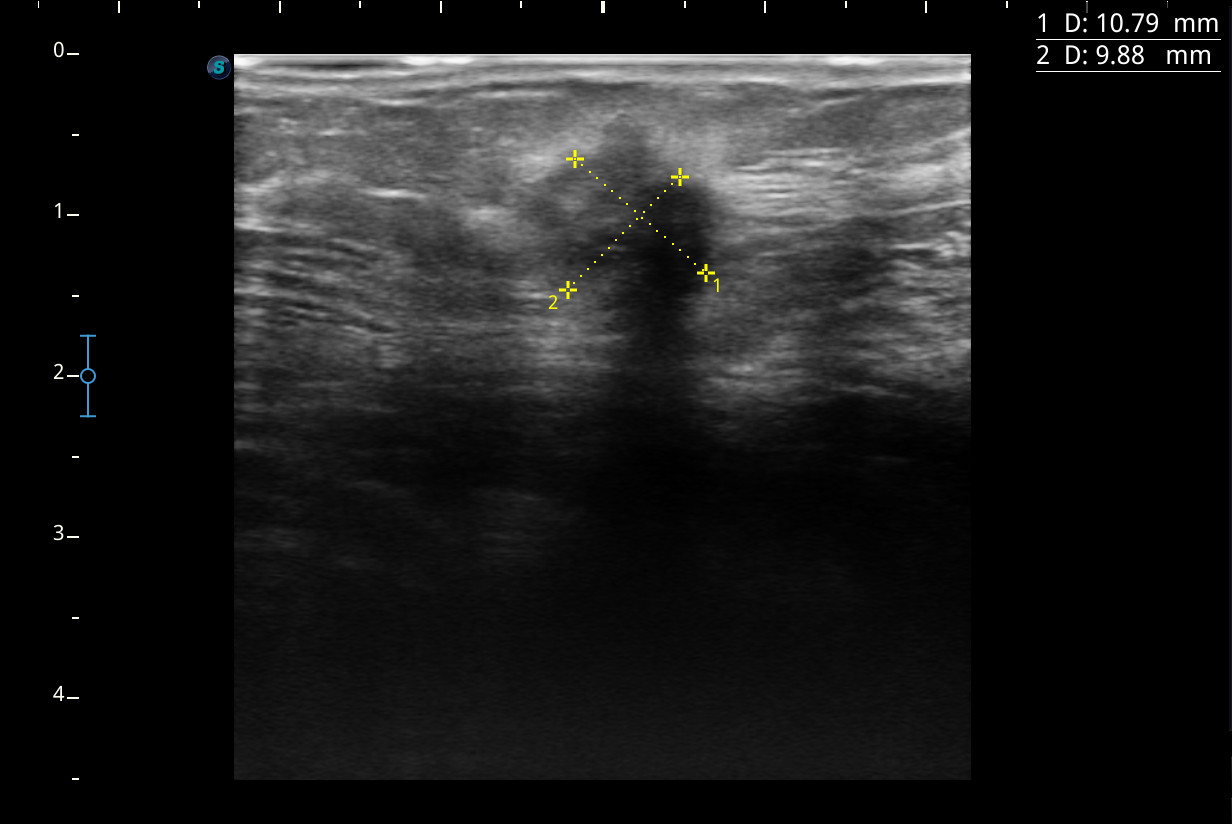

Hallazgos ecográficos

Se visualiza un nódulo mal delimitado, de bordes irregulares y algo espiculados, con captación doppler color sobre todo en periferia y posibles focos centrales de necrosis, compatible con posible neoplasia.